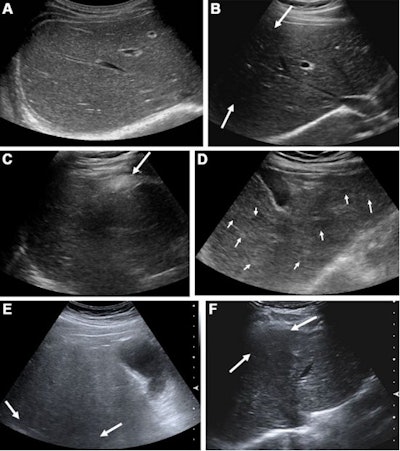

Park and colleagues wanted to investigate ultrasound's detection power and HCC occurrence, using the ultrasound LI-RADS visualization score in patients with chronic hepatitis B. LI-RADS proposes three levels of visualization scoring that depends on the degree of limitation. Visualization A means no or minimal limitations, visualization B indicates moderate limitations that may obscure small masses, and visualization C means severe limitations that would significantly lower the sensitivity of detecting focal liver lesions.

In addition, they found that parenchymal heterogeneity from advanced cirrhosis was the most common cause of suboptimal visualization on ultrasound (n = 489). Other causes included limited window from overlying organ shadow (n = 341) and limited penetration from fatty liver (n = 200).